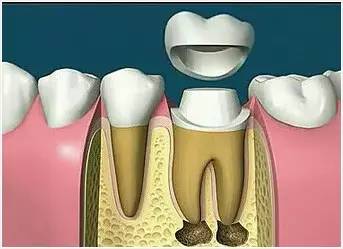

根管治疗是针对牙齿、牙髓、根尖病变的一个治疗过程。通过清除根管内的坏死物质,进行适当的消毒,充填根管,以去除根管内容物对根尖周围组织的不良刺激,防止发生根尖周病变或促进根尖周病变愈合的一种治疗方法。

因牙体缺损过多,导致牙的强度(承受力量的性能)大幅度下降,不能很好地承受咀嚼力量。打桩的目的是增加牙根及牙冠的强度,增加患牙的稳固。

8、完成牙体修复

X线片显示根管充填完好,行暂时或永久牙体修复,带上牙冠,保护患牙。至此根管治疗才可算完成,同时根管治疗后还需复诊,一般周期可为3个月、半年、1年、2年或更长。